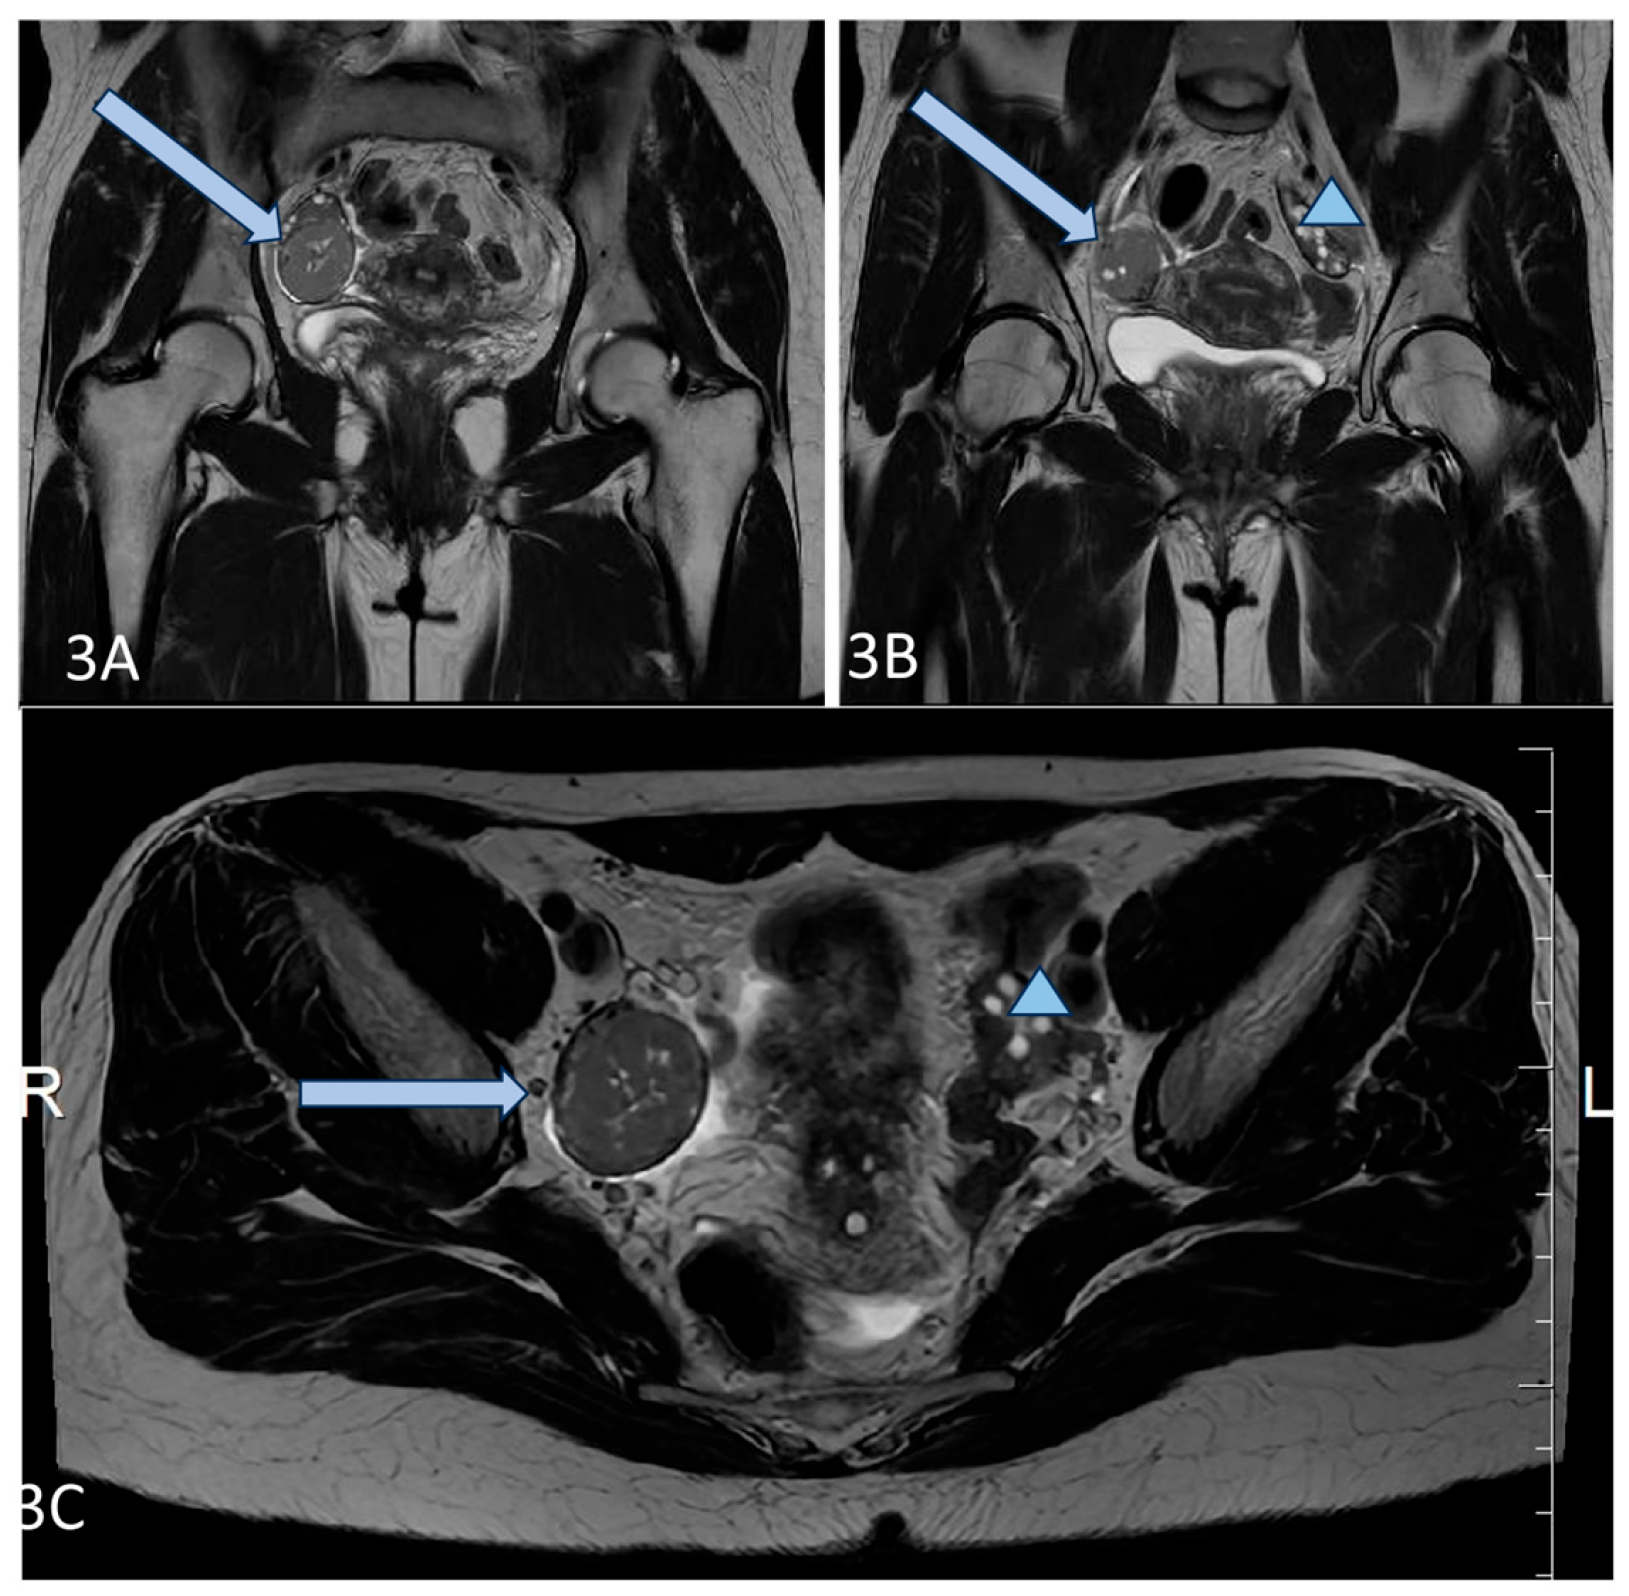

A 25-year-old lean Caucasian woman (BMI 19.0 kg/m2) was referred to the Endocrine Department because of hirsutism. After menarche at the age of 16 years, she had suffered from oligomenorrhea. Oral contraceptive treatment had been provided, but stopped because of the development of breast fibroadenoma. However, over the last three years, the menstrual pattern has become regular. She complained of slightly increased non-progressive hair growth on androgen-dependent zones since puberty, which was treated locally by a dermatologist. Polycystic ovary syndrome was suspected, based on her complaints (Table 1). Laboratory results showed upper-normal testosterone and increased levels of 17-OH progesterone. Therefore, congenital adrenal hyperplasia was excluded through a short Synacthen test. The blood count, blood glucose, lipid panel, and routine biochemical parameters, as well as thyroid function, were normal, while the AMH was significantly increased (23 ng/mL). A pelvic ultrasound revealed uterus didelphys with two separated cervices and a septated distal vagina. The ovaries were significantly increased in volume (“double ovaries”) but without pathological findings. The subsequent magnetic resonance imaging (MRI) (Figure 1) confirmed the ultrasound description. No tumor was found in the ovaries, and the investigated tumor markers (CEA, hCG, alpha-fetoprotein, LDH, and Ca-125) were in the reference ranges.

Figure 1. (AD) Axial T2FSE Fat Sat and T2FSE images (A,B) of the patient demonstrate uterus didelphys (orange star) and double bilateral ovaries (arrows). A sagittal T2 FSE image (C) shows double, partially fused ovaries. Two separate uterine cavities and bilateral ovaries are seen in the paracoronal oblique plane, parallel to the uterine axis (D).